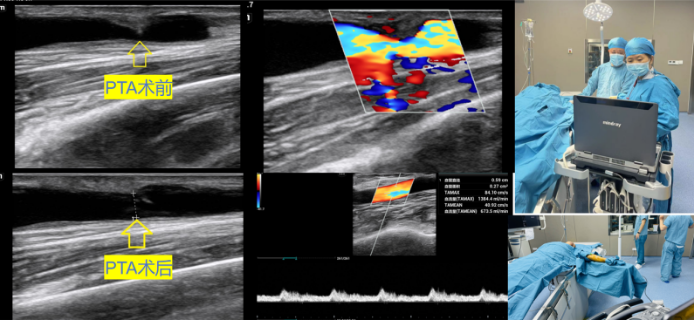

在超声医学中心刘莉主任和穆靓副主任的安排下,韦爱华副主任医师利用便携式超声诊断仪床旁配合闫晓辉副主任医师,为该患者顺利进行自体动静脉内瘘狭窄球囊扩张术。术后恢复良好,狭窄处的管径从1.3mm增宽到4.0mm,进行穿刺内瘘血液透析治疗血流量充足,泵控血流量达250ml/min。

PTA手术是处理动静脉内瘘狭窄、闭塞的一种治疗方法,具有微创、安全、并发症少、重复性高等优势,不仅能够保护通路血管的连续性和完整性,并且最大限度保存患者有限的血管资源,降低了外科手术并发症发生的风险,因此成为内瘘狭窄、闭塞的一线治疗方法。与传统造影相比,PTA手术可实时动态观察导丝、球囊导管与血管之间的关系,动态监测血流动力学参数变化以了解内瘘功能,准确定位病变部位,根据血管直径选择合适球囊,避免造影剂不良反应的发生等。